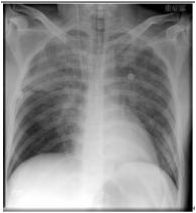

3. 病人18歲女計程車無線呼叫員, 到院主訴有五天的間 歇性燒熱及寒顫(chillness), 並合併頭痛、雙眼後疼痛及全身肌疼, 經初步診斷腦膜炎, 病人拒絕腰椎穿刺檢查, 乃試用抗生素後回家療養。 唯症狀仍舊, 尚有噁心、嘔吐, 並先後在左大拇指及右小趾出現疼痛紅斑(如圖A及B所示)。既往病史有二尖瓣膜脫垂及閉鎖不全。理學所見身高:162cm;體重:45Kg;BP:105/67mmgHg;T/P/R: 39.8C/155/18。未見Meningeal signs. 頸部末見異常, 心尖在left 5th ICS, mid-clavicular line, 有Grade III/VI Pansystolic murmur. S1及S2正常。胸、腹都無不正常。實驗室檢查: WBC:4.39x k/uL,有left shifting;RBC:5.12 x M/uL;Hb:11.0 g/dL;Platelets:130 x K/uL;其血液細菌培養結果如與胸部X光詳見附圖C、D。心電圖如附。本病人經過下列臨床處置